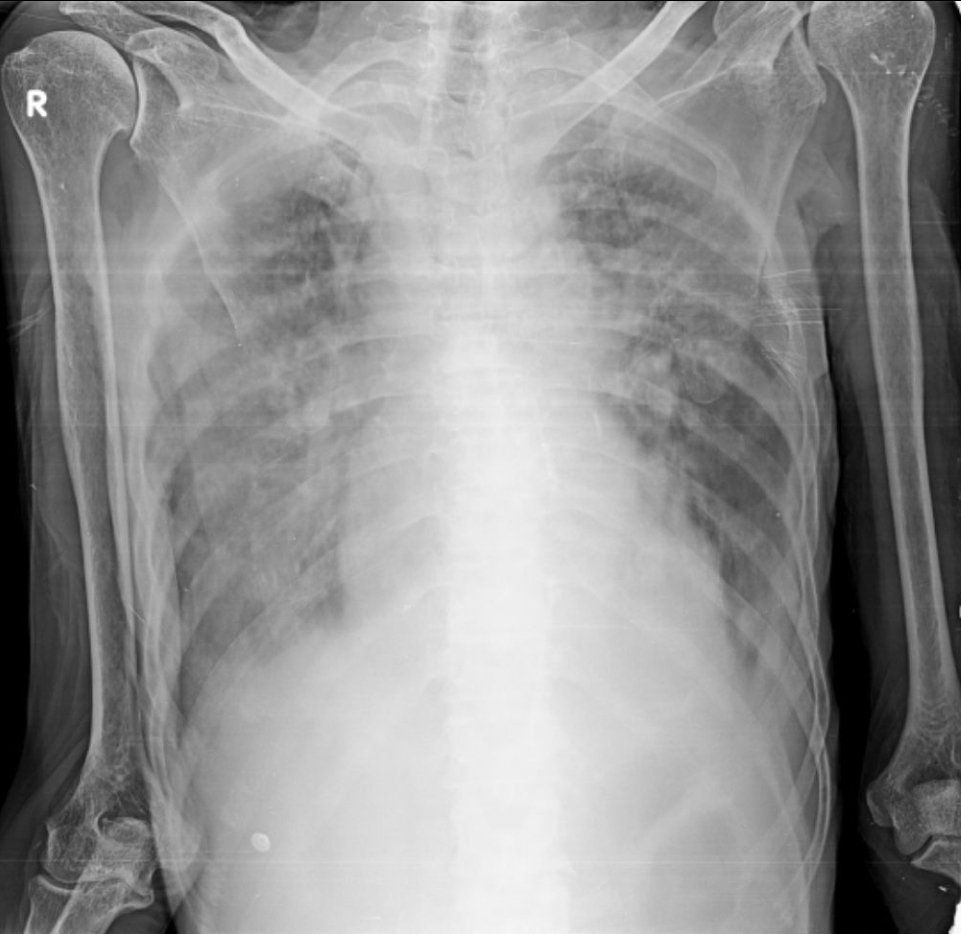

Xray